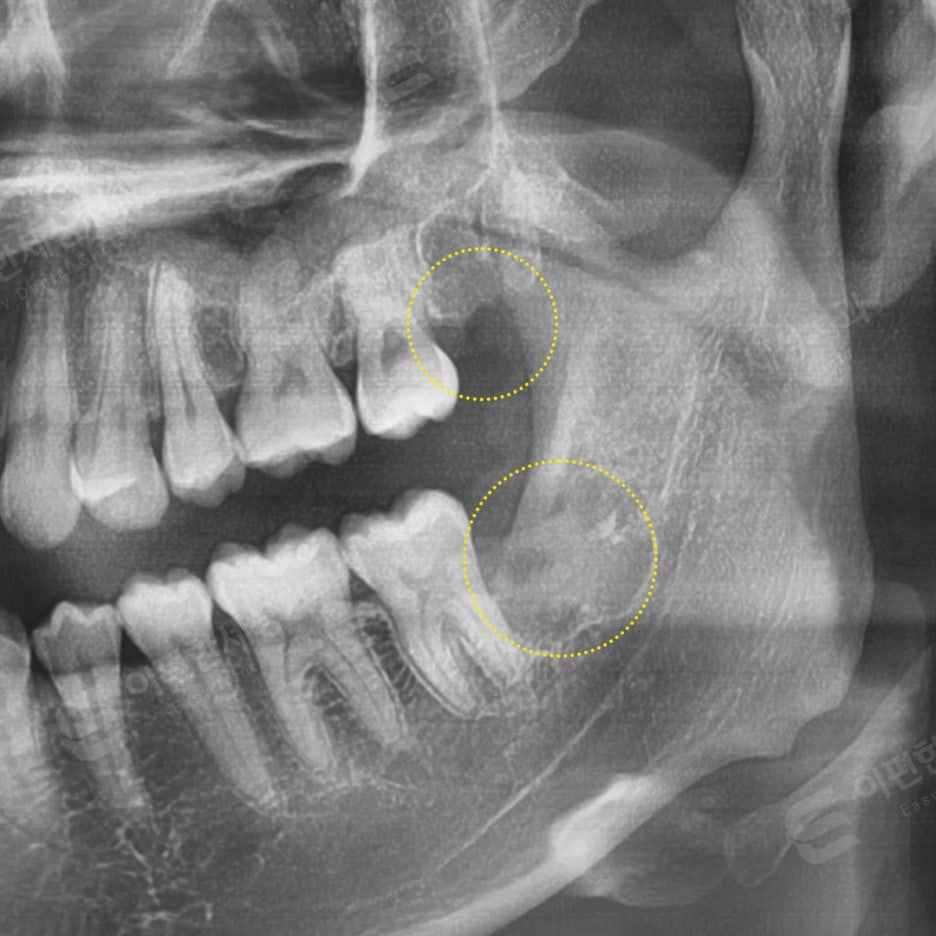

촬영 일자 24. 02. 17

인터넷 검색 후 내원, 당일 발치 케이스

#48 복잡매복 발치

치아 뿌리와 신경관 가까워 보여

CT 촬영 후 발치

#18 일반 발치